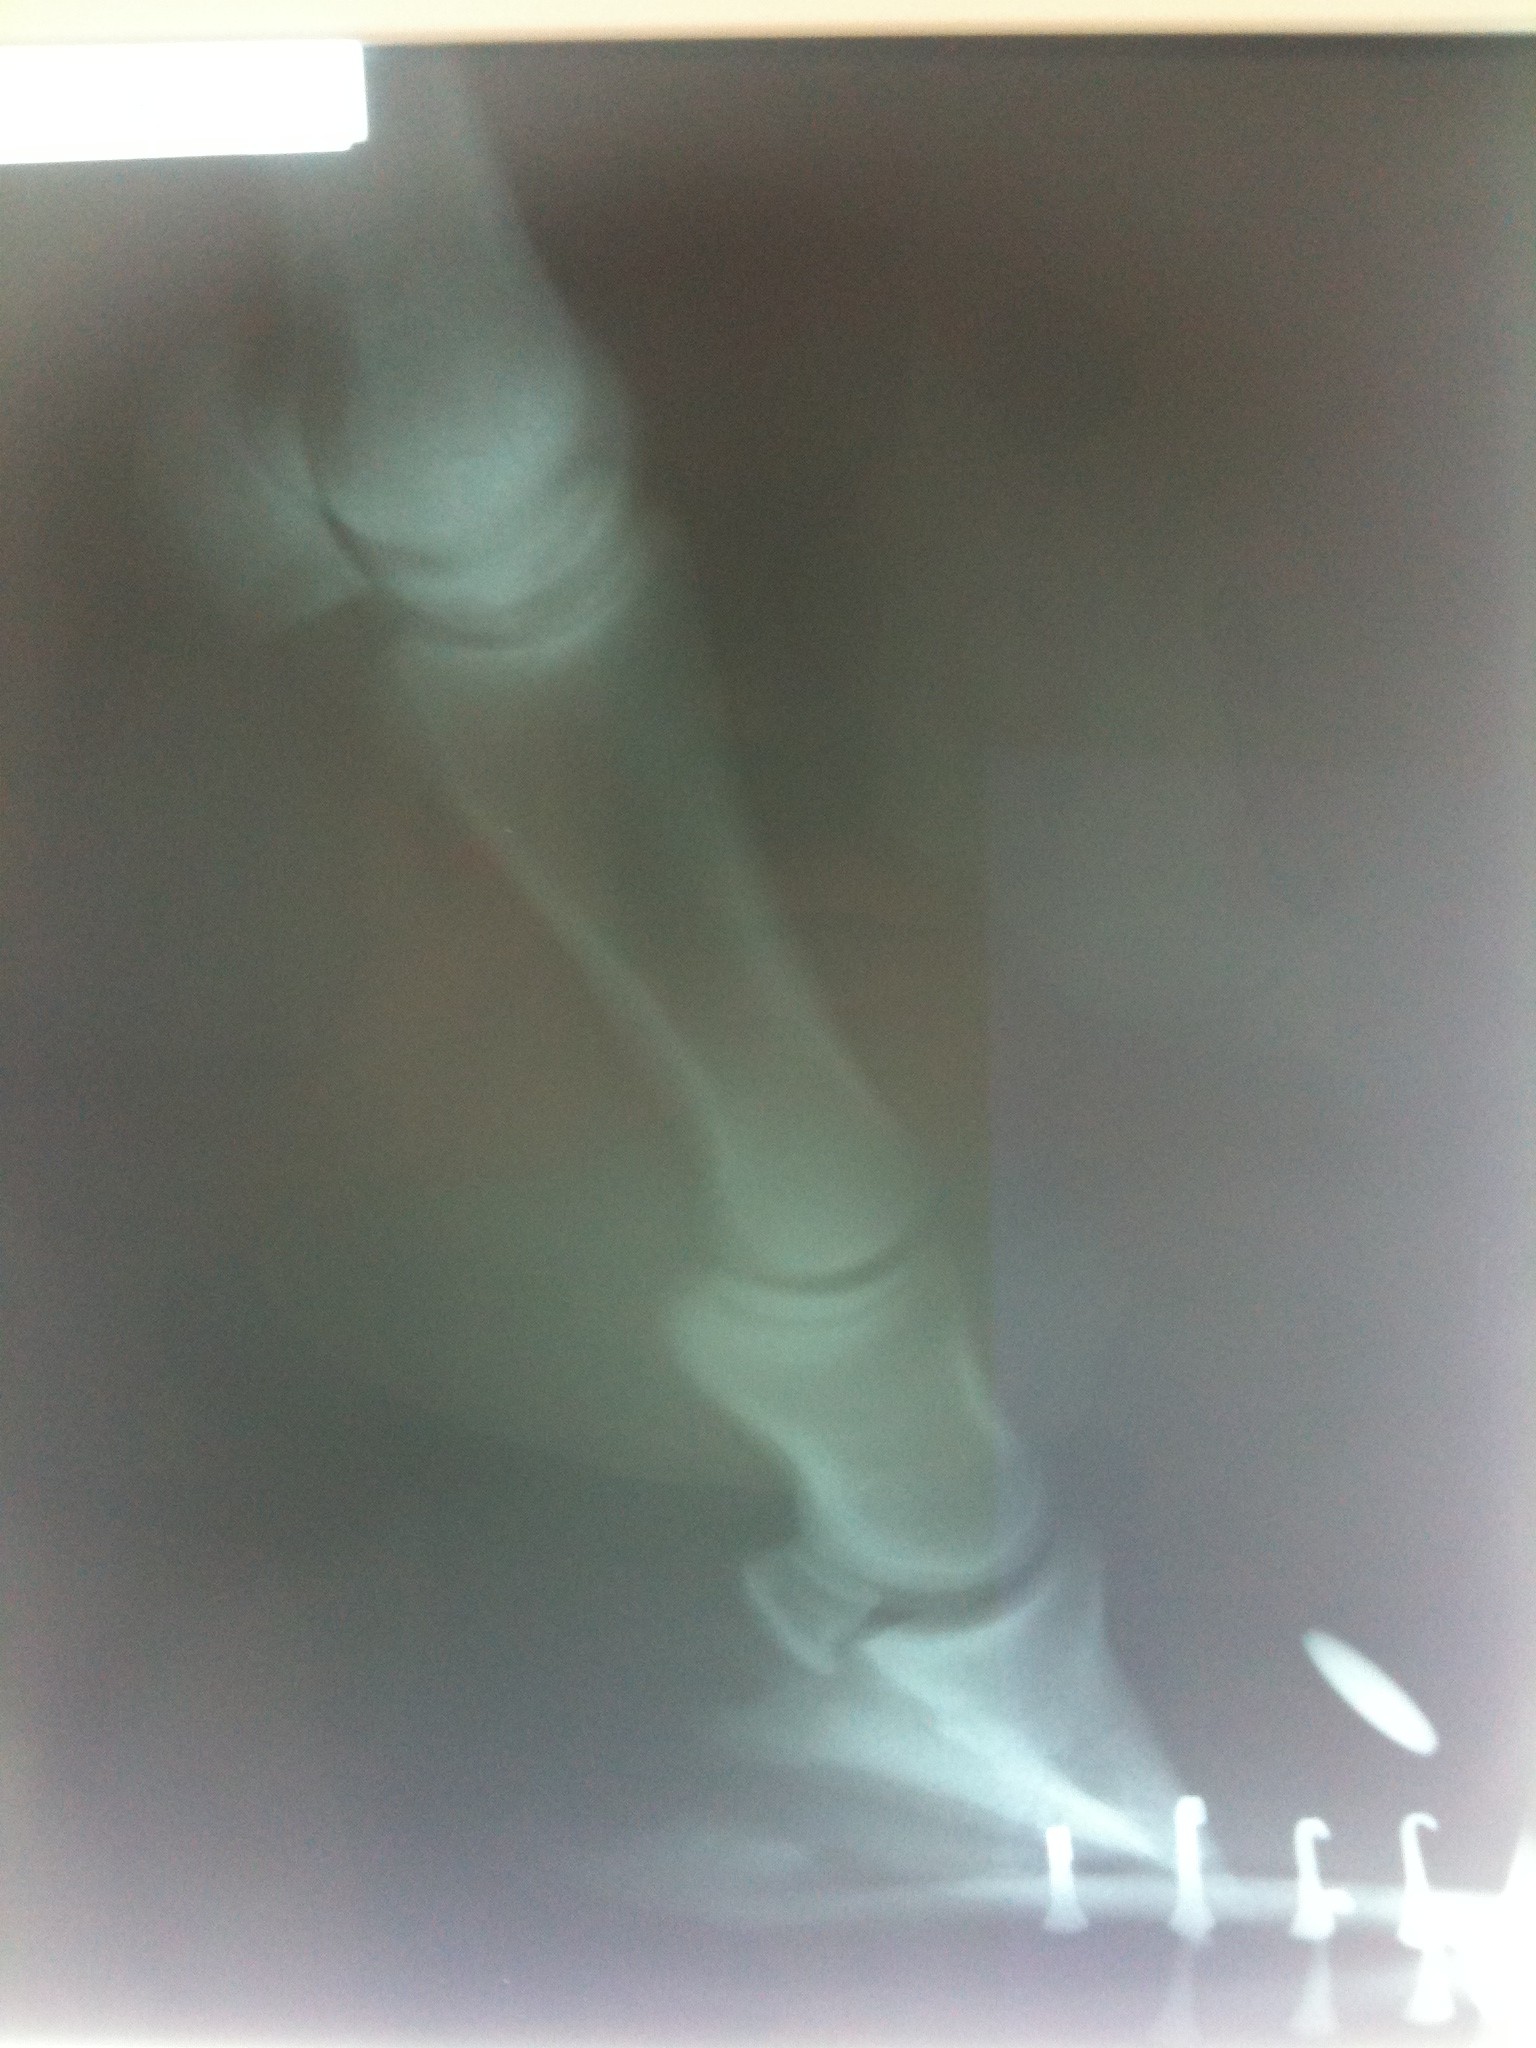

York ended up losing 3/4 of his hoof wall on the LF. His hoof wall jammed up into his coronary band and had to be filed and cut away to allow for new hoof to grow. The large wedge of dead laminar tissue between the detached hoof wall and the coffin bone was acting as a perfect breeding ground for bacteria so most of it was removed as well.

Within a few days I saw a dramatic improvement in York’s overall condition and his hoof seemed to be stabilizing. The drainage decreased substantially and I could see where new healthy tissue was growing over his damaged coronary band. My farrier, Cecilia Adamson was finally able to remove the racing plates on York’s other 3 hooves and get them trimmed. York was so cooperative despite his discomfort.

With continued Xango soaks, in 2 weeks the proud flesh at the coronary band completely resolved. York was starting to put some weight on the foot and all was looking good but York still had some rough stops to get through. More to come. Madalyn